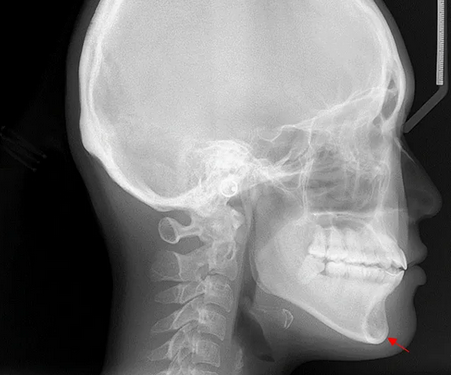

16

Q

_____ is required to determine the mandibular plane angle

A

cephalometric imaging